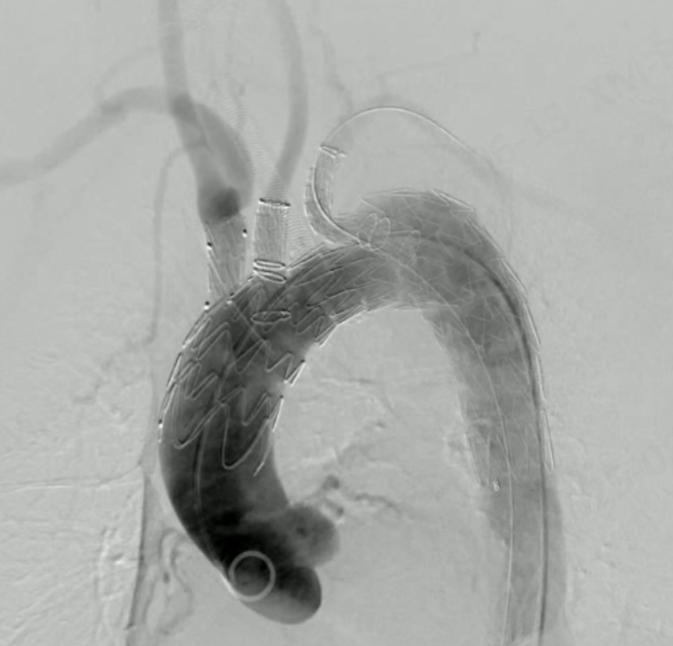

▲术后造影

Hector?胸主多分支支架获批欧盟定制许可,也将进一步有力推动公司分支型支架产品在欧盟地区及其他海外市场的准入和推广应用。该产品目前已在瑞士、意大利、德国成功开展了多例临床应用,手术效果良好。